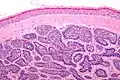

Micrograph of dermal cylindroma in H&E stain. -

Dermal cylindroma. Puzzle-like distribution of tumour foci.

Dermal cylindromas are:

- Dermal lesions consisting of nests of cells that are surrounded by hyaline (i.e., glassy, eosinophilic, acellular) material and have:

- Hyperchromatic nuclei that may palisade (columnar nuclei arranged around the periphery of the cell nests with their short axis tangential to the nest periphery), and

- Cells with lighter staining ovoid nuclei at their centre.